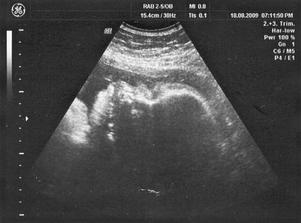

12/8 09 PORADNA PRO RIZIKOVÁ TĚHOTENSTVÍ 34 + 3 tt - váha malé 1.796 + - 262 g - váha odpovídá o týdnu méně než jsem nyní, tak jsem ráda že díky cukrovce nečekám nějakou cvalici 🙂), placenta je stále ok a plodové vody mám příměřeně 🙂), jinak za mého dr. zastupovala dr. Oborná z CAR která mi dělala mé 2. IVF tak jsme si úžasně pokecali a popřála mi ať mi vše dobře dopadne, prý je moje přirozené těhu malý boží zázrak tak jsem byla dojatá 🙂) ... byla to má poslední riz. poradna, předali mě už na porodní sál

18/8 09 PORADNA 35 + 2 tt - poslední poradna, první natáčení monitoru - srdíčko i pohyby ok, na utz jsme si raději nechali potvrdit pohlaví abysme nebyli na por. sále překvapení tak je to 100% holka, dr. mi ukázala pohlaví a to bych poznala i já 🙂) Mája už se nám moc ukazovat nechtěla, pořád si dávala ručenky před obličej, z poslední poradny je i poslední fotečka Máji na památku ... už se nám to blíží 🙂)